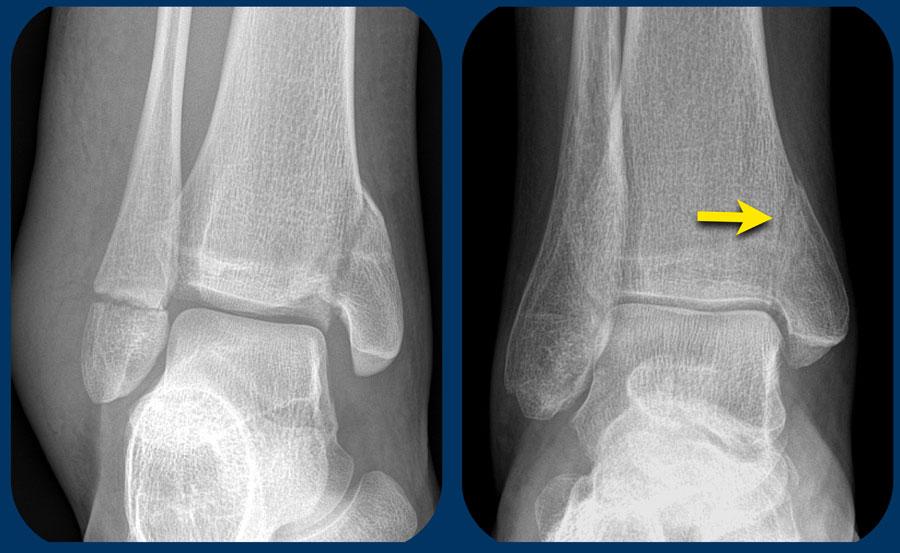

Đôi khi chúng ta may mắn vì đường gãy xương mác có thể nhìn thấy trên X-quang cổ chân.

Khi đó chúng ta biết mình đang đối mặt với gãy xương Weber C giai đoạn 3 không ổn định.

Trong trường hợp này, có sự giãn rộng khoang sáng phía trong (medial clear space) giữa mắt cá trong và xương sên, cho thấy đứt dây chằng bên trong (giai đoạn 1).

Chúng ta phải giả định rằng cũng có đứt khớp chày mác xa phía trước (giai đoạn 2).

Ngoài ra cũng có thể có tổn thương giai đoạn 4 ở khớp chày mác xa phía sau.